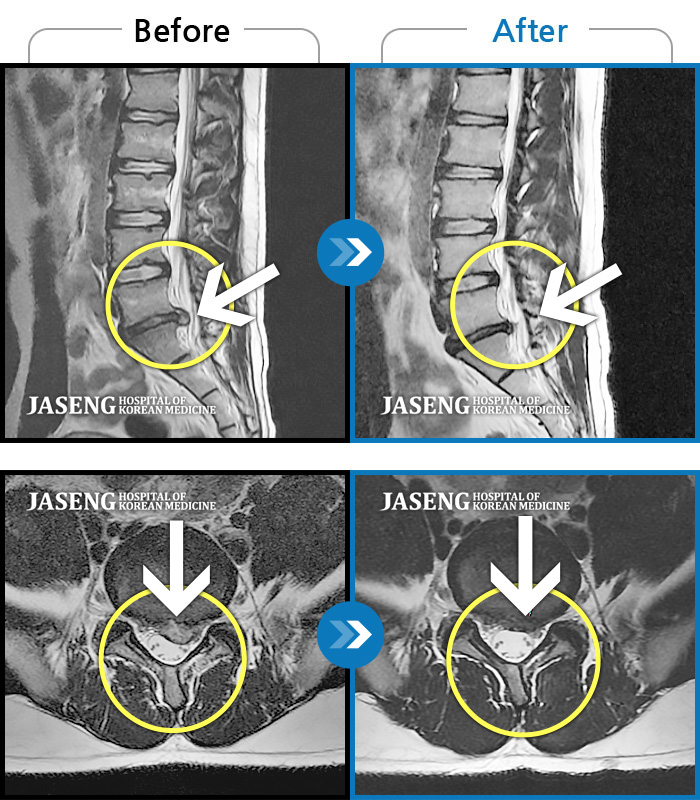

Before

After

환자에게 사전 동의를 받아 동일 조건에서 촬영되었습니다.

개인에 따라 치료 후 부작용이 발생할 수 있으니 의료진과 상담 후 치료를 진행하시기 바랍니다.

허리 통증, 똑바로 서려고 하거나 걸을 때 양쪽 허벅지와 고관절 시큰거림

좌측 허리 통증 및 좌측 다리 저림